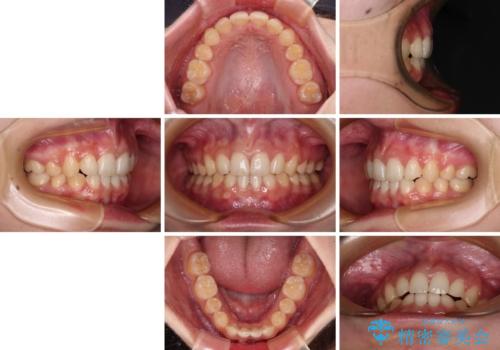

通常の抜歯矯正と抜くべき歯の位置が異なるため、咬みにくさが残ってしまうのではないかと懸念されましたが、咬み合わせに違和感なく、スムーズに治療を終えることができました。